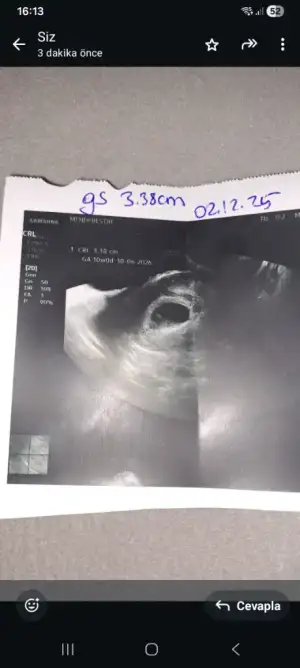

Ben yeni üye oldum. Ara ara girip takip ediyordum ama bugün doktor kontrolü de olunca artık kesinleşince üye olayım yeni arkadaşlar edineyim dedim

Bizim biraz sürpriz oldu. Hiç beklemiyorduk. Umarım hepimiz sağlıkla alırız bebeklerimizi